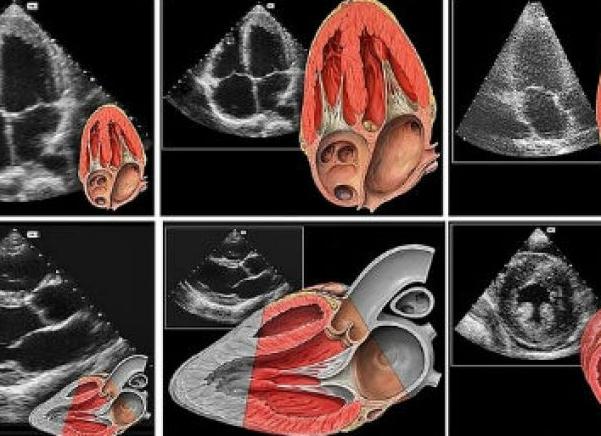

ЭХО сердца (УЗИ)- один из самых лучших методов диагностирования сердечно-сосудистых заболеваний, ведь он предоставляет максимум информации по болезням в кратчайшие сроки. Основные принципы его действия — волны отражаются от структур разнообразной плотности, меняя при этом скорость распространения и длину волны. Эти волны улавливаются оборудованием и после компьютерной обработки создают на экране изображение сердца.

Существует несколько типов эхокардиографии, каждая из которых использует звуковые волны для создания изображений сердца. В отличие от эхокардиографических исследований, эхокардиография не включает радиацию. Трансторакальная эхокардиография является наиболее распространенным типом. Трансторакальная эхокардиограмма включает размещение устройства, называемого преобразователем в сундук, который посылает ультразвук через сундук к сердцу. Когда ультразвуковые волны поражают структуры сердца, компьютер на машине эхокардиографии превращает их в изображения сердца.

Эхо ЭКГ сердца выполняется специальным электронным устройством – так называемым преобразователем. Прибор вплотную прикладывается к грудной клетке и приводится в действие. Преобразователь – это генератор волн ультразвукового спектра.

Излучаемые преобразователем волны проходят во внутрисердечную структуру, отражаются от сердечных тканей и возвращаются обратно в генератор. Посредством специального оснащения, преобразователь обрабатывает полученные данные и выводит их на монитор в виде объёмной картинки.

ЭхоКГ (УЗИ сердца) представляет собой ультразвуковую диагностику, которая заключается в сканировании органа и отображении его изображения. Обследование ультразвуком разных органов и тканей происходит путем отражения от их поверхности ультразвуковых волн, которые излучает датчик. В это время на мониторе происходит построение изображения. Специалист УЗИ оценивает состояние сердца, его строение, проверяет наличие нарушений.

ЭхоКГ производится прибором особого назначения – ультразвуковым датчиком. Волны, исходящие от датчика, проникают во внутрисердечную полость, отражаются от тканей и возвращаются обратно в аппарат, где происходит анализ данных и выведение их на экран.

Часто пациенты интересуются, ЭхоКГ и УЗИ сердца – одно и то же или же нет. Эхокардиографию называют УЗИ сердца, так как она основана на ультразвуковом обследовании сердца, но при этом она включает и элементы электрокардиографии. Во время обследования одновременно проводятся процедура УЗИ и ЭКГ, что значительно повышает информативность. Метод основывается на способности тканей тела отражать ультразвук и возвращать его обратно в датчик.